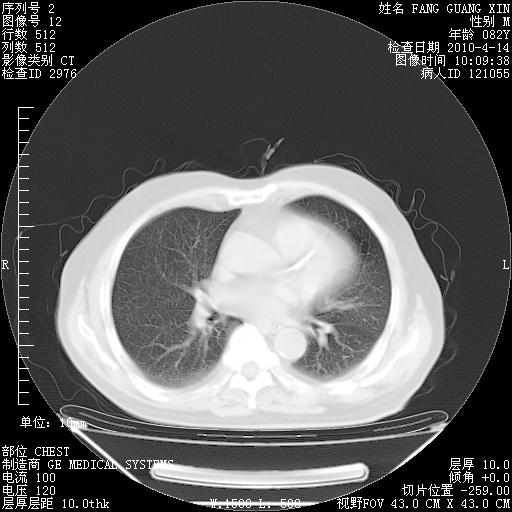

肺部CT平扫未见异常。